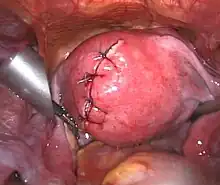

Submucosal fibroid in hysteroscopy

Treatment of an intramural fibroid by laparoscopic surgery After treatment of an intramural fibroid by laparoscopic surgery

After treatment of an intramural fibroid by laparoscopic surgery